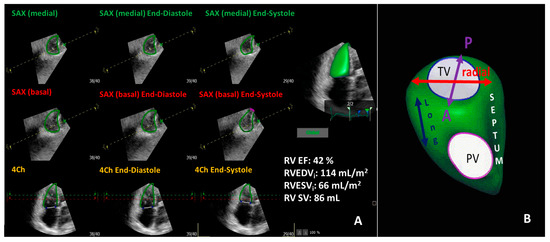

- Shimada, Y.J.; Shiota, M.; Siegel, R.J.; Shiota, T. Accuracy of right ventricular volumes and function determined by three-dimensional echocardiography in comparison with magnetic resonance imaging: A meta-analysis study. J. Am. Soc. Echocardiogr. 2010, 23, 943–953. [Google Scholar] [CrossRef]

- Sugeng, L.; Mor-Avi, V.; Weinert, L.; Niel, J.; Ebner, C.; Steringer-Mascherbauer, R.; Bartolles, R.; Baumann, R.; Schummers, G.; Lang, R.M.; et al. Multimodality comparison of quantitative volumetric analysis of the right ventricle. JACC Cardiovasc. Imaging 2010, 3, 10–18. [Google Scholar] [CrossRef]

- Addetia, K.; Muraru, D.; Badano, L.P.; Lang, R.M. New Directions in Right Ventricular Assessment Using 3-Dimensional Echocardiography. JAMA Cardiol. 2019, 4, 936–944. [Google Scholar] [CrossRef]

- Maffessanti, F.; Muraru, D.; Esposito, R.; Gripari, P.; Ermacora, D.; Santoro, C.; Tamborini, G.; Galderisi, M.; Pepi, M.; Badano, L.P. Age-, body size-, and sex-specific reference values for right ventricular volumes and ejection fraction by three-dimensional echocardiography: A multicenter echocardiographic study in 507 healthy volunteers. Circ. Cardiovasc. Imaging 2013, 6, 700–710. [Google Scholar] [CrossRef]

- Tamborini, G.; Marsan, N.A.; Gripari, P.; Maffessanti, F.; Brusoni, D.; Muratori, M.; Caiani, E.G.; Fiorentini, C.; Pepi, M. Reference values for right ventricular volumes and ejection fraction with real-time three-dimensional echocardiography: Evaluation in a large series of normal subjects. J. Am. Soc. Echocardiogr. 2010, 23, 109–115. [Google Scholar] [CrossRef]

- Wang, S.; Wang, S.; Zhu, Q.; Wang, Y.; Li, G.; Kong, F.; Yang, J.; Ma, C. Reference Values of Right Ventricular Volumes and Ejection Fraction by Three-Dimensional Echocardiography in Adults: A Systematic Review and Meta-Analysis. Front. Cardiovasc. Med. 2021, 8, 709863. [Google Scholar] [CrossRef]

- Lakatos, B.K.; Nabeshima, Y.; Tokodi, M.; Nagata, Y.; Tősér, Z.; Otani, K.; Kitano, T.; Fábián, A.; Ujvári, A.; Boros, A.M.; et al. Importance of Nonlongitudinal Motion Components in Right Ventricular Function: Three-Dimensional Echocardiographic Study in Healthy Volunteers. J. Am. Soc. Echocardiogr. 2020, 33, 995–1005.e1. [Google Scholar] [CrossRef]

- Tokodi, M.; Staub, L.; Budai, Á.; Lakatos, B.K.; Csákvári, M.; Suhai, F.I.; Szabó, L.; Fábián, A.; Vágó, H.; Tősér, Z.; et al. Partitioning the Right Ventricle into 15 Segments and Decomposing Its Motion Using 3D Echocardiography-Based Models: The Updated ReVISION Method. Front. Cardiovasc. Med. 2021, 8, 622118. [Google Scholar] [CrossRef] [PubMed]